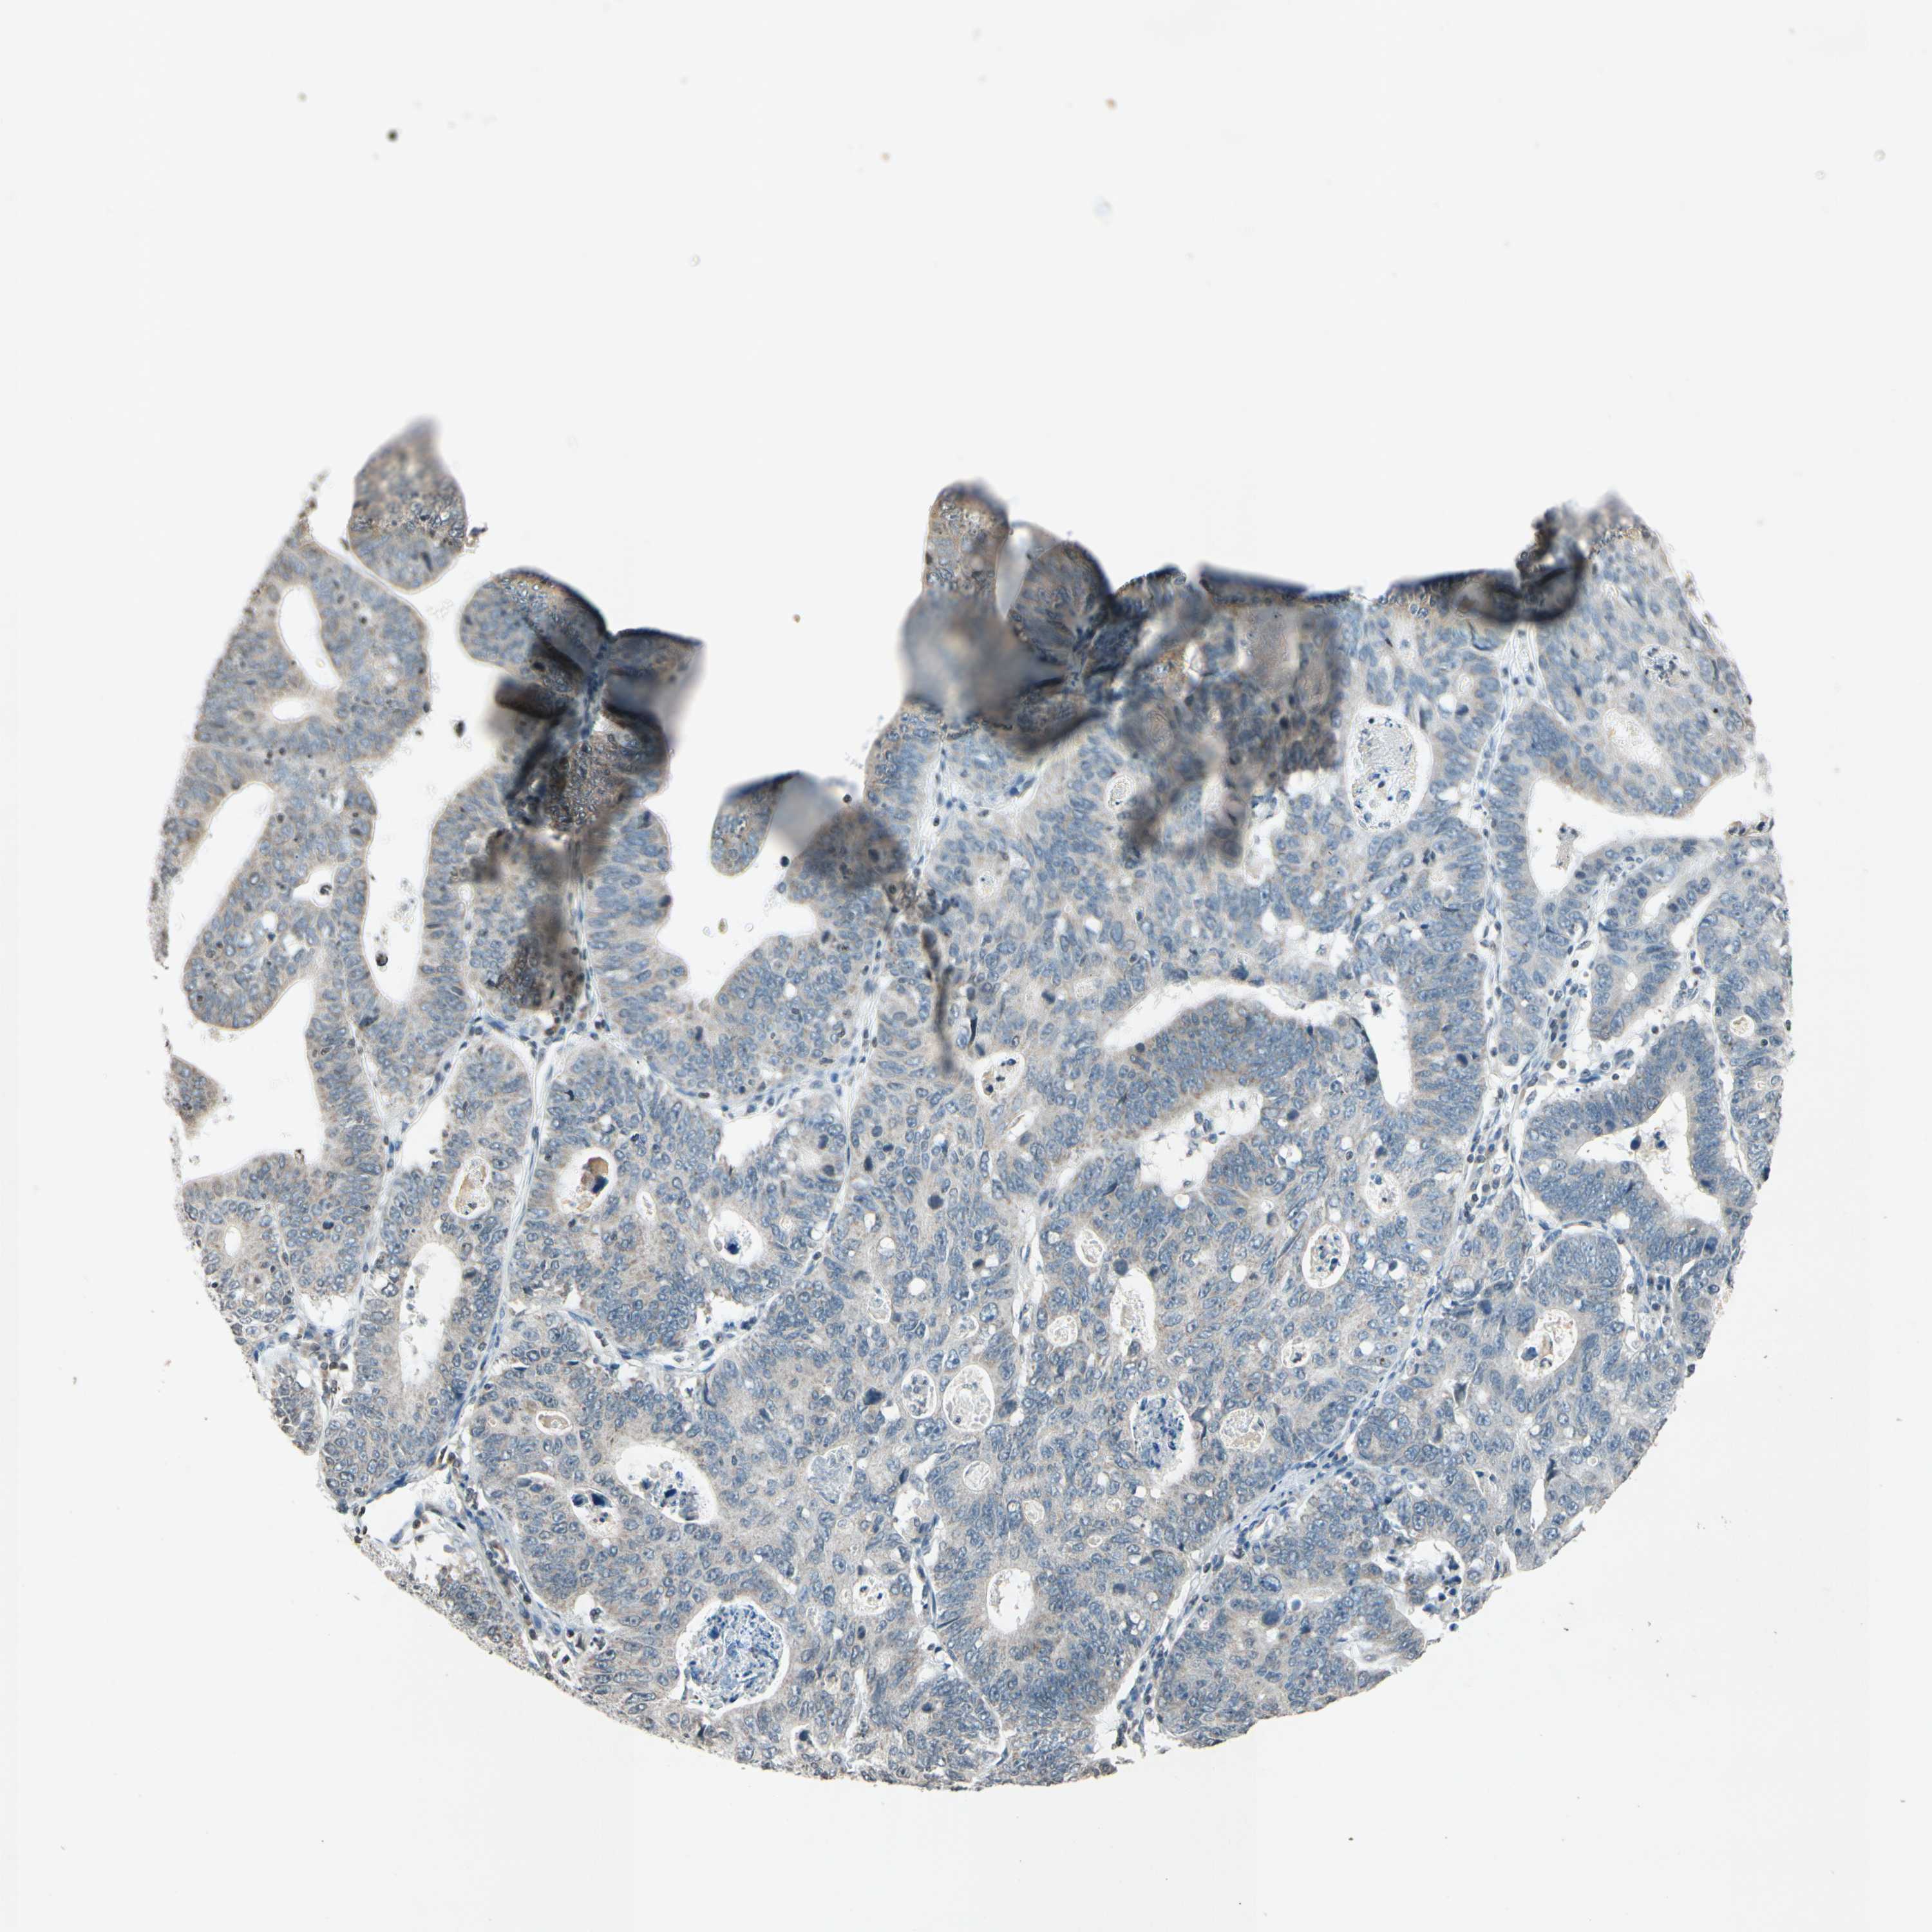

STOMACH CANCER - Protein expressioni

A mouse-over function shows sample information and annotation data. Click on an image to view it in a full screen mode. Samples can be filtered based on level of antibody staining by selecting one or several of the following categories: high, medium, low and not detected. The assay and annotation is described here.

Note that samples used for immunohistochemistry by the Human Protein Atlas do not correspond to samples in the TCGA dataset.

Antibody stainingi

Antibody staining in the annotated cell types in the current human tissue is reported as not detected, low, medium, or high, based on conventional immunohistochemistry profiling in selected tissues. This score is based on the combination of the staining intensity and fraction of stained cells.

Each image is clickable and will lead to virtual microscopy that enables deeper exploration of all samples and also displays staining intensity scores, fraction scores and subcellular localization as well as patient and tissue information for each sample.

Antibody HPA013166

Antibody CAB009789

Staining

High

Medium

Low

Not detected

Intensity

Strong

Moderate

Weak

Negative

Quantity

>75%

75%-25%

<25%

None

Location

Nuclear

Cytoplasmic/membranous

Cytoplasmic/membranous,nuclear

Adenocarcinoma, NOS

Adenocarcinoma, High grade